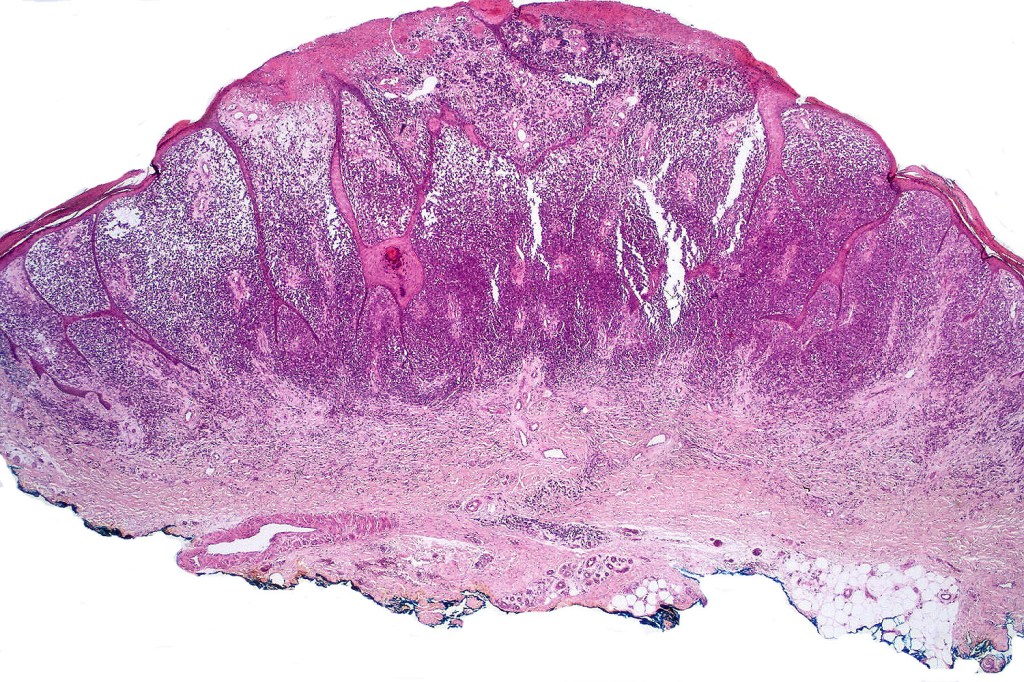

A rare variant of nevoid melanoma wherein the tumor cells have scant cytoplasm, and basophilic, hyperchromic nuclei mimicking type B nevus cells. Typically, the tumor cells are positive for S100, Mart-1 & HMB45. It is of no prognostic importance. It is one of the more often encountered melanoma variants in giant congenital nevi & can be mistaken for a congential nevus if the lesion is dismissed as benign at scanning magnification. In the absence of clinical history in metastatic lesions, the differential diagnoses of lymphoblastic leukemina/lymphoma, neuroendocrine carcinoma, small cell carcinoma, neuroblastoma, malignant perihperal nerve sheath tumor & Ewing’s sarcoma can be excluded with appropriate immunohistochemistry. Exceptionally small cell melanoma may express neuroendocrine markers